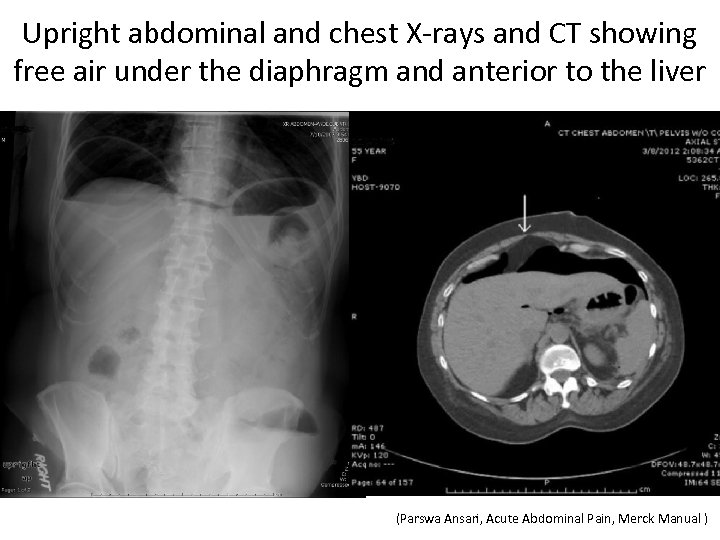

Upright abdominal and chest X-rays and CT showing free air under the diaphragm and anterior to the liver (Parswa Ansari, Acute Abdominal Pain, Merck Manual )